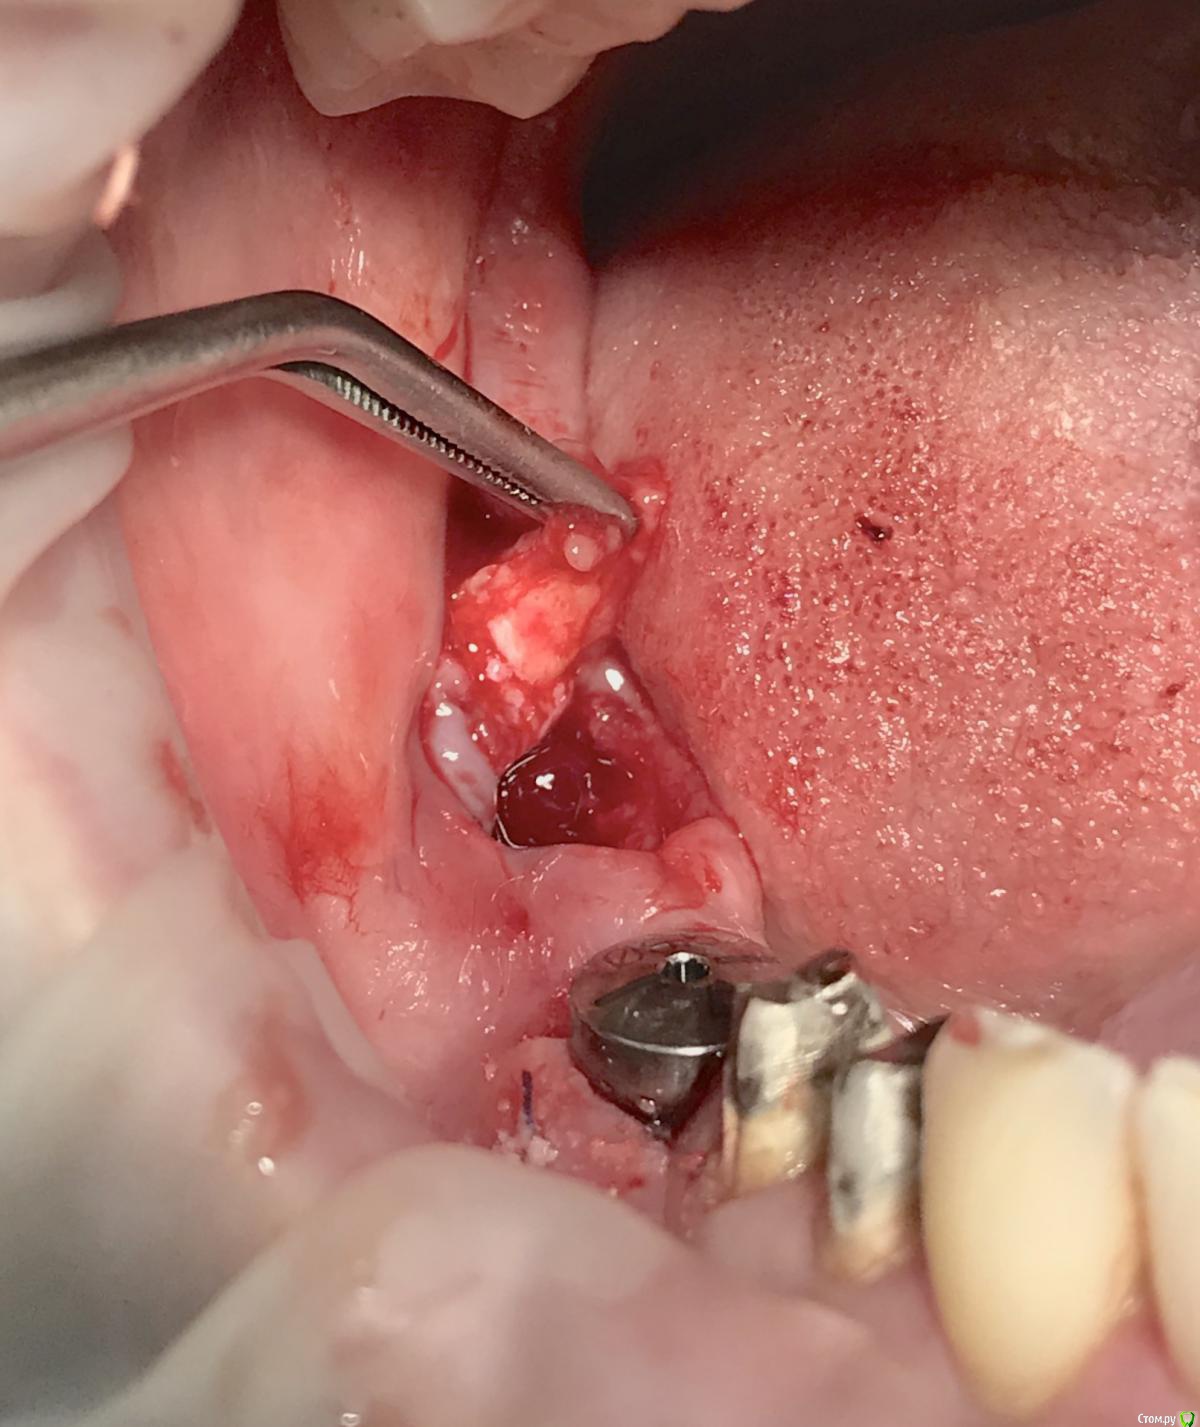

Женька Опубликовано 17 февраля, 2023 Поделиться Опубликовано 17 февраля, 2023 (изменено) И в догоночку 1.8... удаление зуба - 5 минут, удаление верхушки - 2 часа. Зуб полная ретенция, лежал близко, но прямо под пазухой, плёвое дело! отломался нёбный апекс, борьба с кровотечением, ничего не видно, отмылся - вроде видно. Ковырялочка рутпикером, вижу что корень смещается только в одном направлении-в сторону пазухи и уже прямо под границы лунки уходит от меня. В итоге ковырялся-ковырялся, пытался достать хоть как-то. В конце плюнул, распилил перегородку в лунке в глубине и сместил в лунку. А дальше чуть не потерялся апекс в мягких тканях . Но достал, главное что видно теперь всё! p.s. это таже самая пациентка) Завтра ещё скину, что-то на этой неделе прям везёт, из 3х зубов, всё три со сломанными апексами) Изменено 17 февраля, 2023 пользователем Женька 1 Ссылка на комментарий